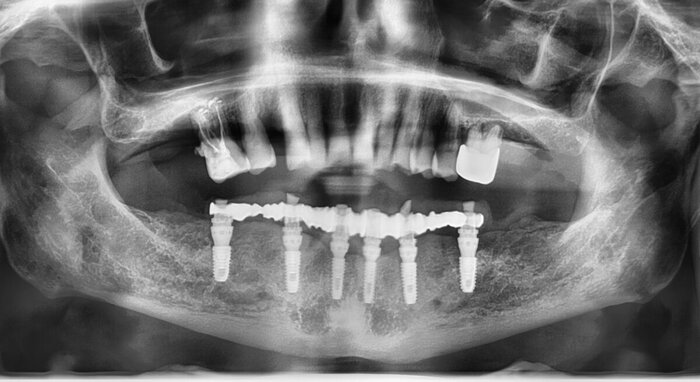

Пока верх не закончен, можно переходить к низу. Тут всё проще (как это часто и бывает). Выбор сделан в пользу тотальной работы на 6 имплантатах (сверху, по итогу, будет то же самое).

Часа через 2.5-3 имплантаты были установлены.

Результат такой - торки получены эталонные везде, кроме двух крайних имплантатов слева (3.4 и 3.6). Но не страшно, сверху зубов-антогонистов нет, нагрузки на протез не будет серьёзной. Да и "всё на 6" прощает подобное.

Протез будет с розовой десной и-за дефицита тканей (FP3).

Устанавливали 6 имплантатов Андрею Михайловичу за месяц до Нового года:

Сделали КЛКТ:

Что бы точно никаких вопросов не осталось у доктора, сделали ОПТГ:

Всё ок, всё прижилось.